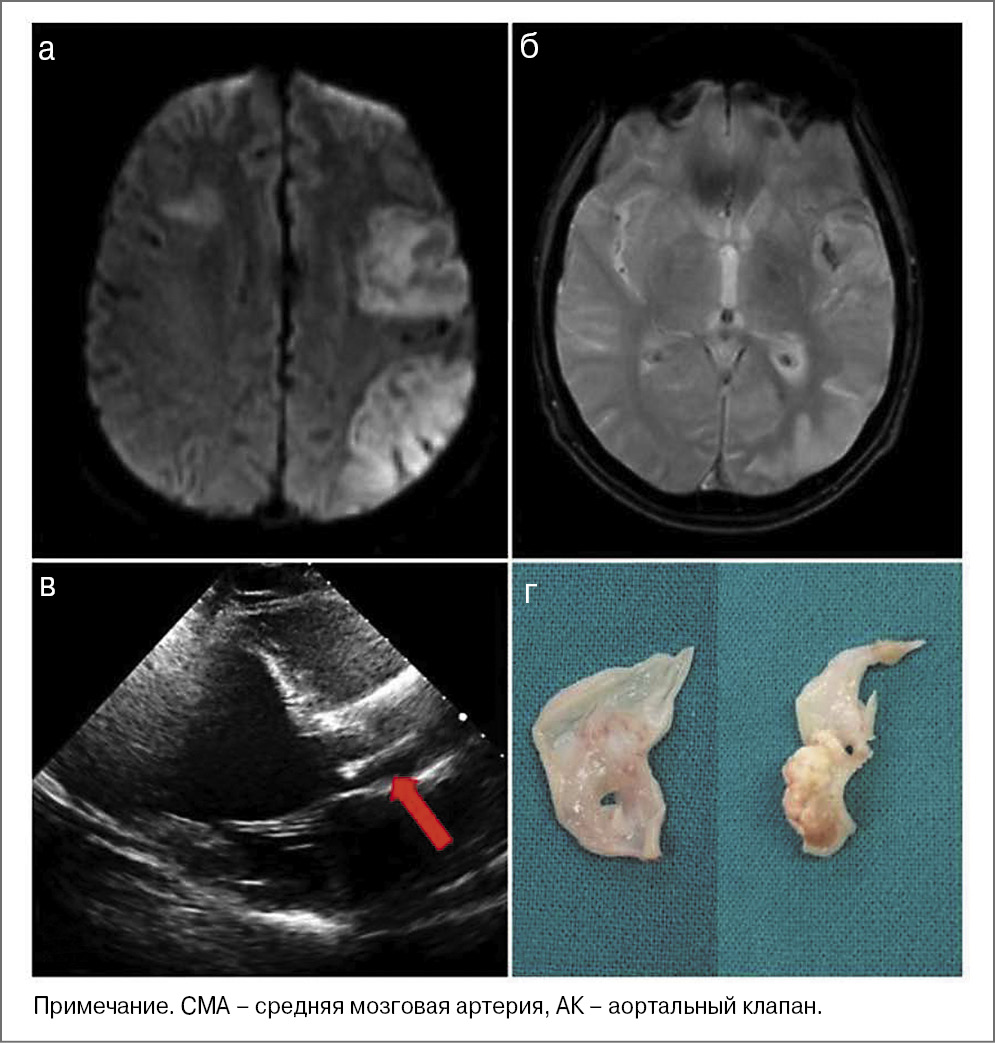

Рис. 3. Клинический пример. Мужчина 63 лет: а – ИИ в бассейне левой СМА (МРТ FLAIR); б – стеноз левой внутренней сонной артерии 70% (ДС); в – стеноз подтвержден (КТА); г – нестабильная атерома (выполнена каротидная эндартерэктомия).

Рис. 4. Клинический пример. Женщина 60 лет, азиатская национальность: а – повторный ИИ в бассейне правой СМА (МРТ DWI); б – первый инсульт в том же бассейне (МРТ FLAIR); в – ДС не выявило ЭКА, однако на селективной ангиографии верифицирован ИКА со стенозом С7-сегмента внутренней сонной артерии и хронической окклюзией М1-сегмента СМА; г – выраженная сеть коллатералей, свидетельствующая об ИКА.